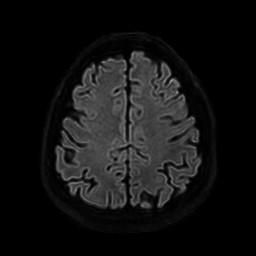

뇌 후두피질위축 봐주시면 감사하겠습니다(mri)

요즘 눈이랑 정신이 좀 이상해서 뇌mri를 찍었는데 이렇게 나오네요.

• 1번 째 사진

정확한 것은 정식 판독을 받아보아야 알 수 있겠습니다만, 개인적인 경험을 토대로 보았을 때에는 위축이 심하다고 보기에는 무리가 있어 보입니다. 뇌실이 비정상적으로 커져 보이지도 않고 뇌의 태두리가 두개골에서 많이 떨어져 있지도 않은 것이, 해당 사진들만 보아서는 위축이 심하고 치매를 의심하여야 한다 어떻다 판단을 내리기는 어려울 것으로 사료됩니다.